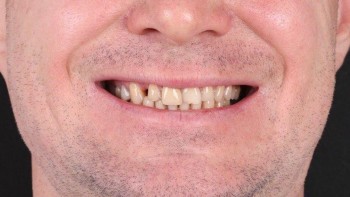

Ведерникова Елена Леонидовна принимает в «ЦЕНТР ГНАТОЛОГИИ ЕЛЕНЫ ВЕДЕРНИКОВОЙ» в Ростове-на-Дону. Главный врач, врач высшей категории, стаж 29 лет. Специализируется на ортодонтии и гнатологии, по которым клиника оказывает 4 услуги. Имеет 5 работ до/после в портфолио. Квалификация специалиста подтверждена 5 лицензиями, сертификатами и наградами. Для уточнения дополнительной информации о специалисте или записи на прием можно позвонить по телефону

5 работ в портфолио

Владеет всеми новейшими американскими технологиями создания голливудской улыбки. Совместно со специалистами Бостонского института проводит комплексное лечение по принципам нейромышечной и эстетической стоматологии, заболеваний височно-нижнечелюстного сустава.